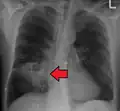

Lung abscesses are often on one side and single involving posterior segments of the upper lobes and the apical segments of the lower lobes as these areas are gravity dependent when lying down. Presence of air-fluid levels implies rupture into the bronchial tree or rarely growth of gas forming organism.

Pulmonary abscess on CT scan -